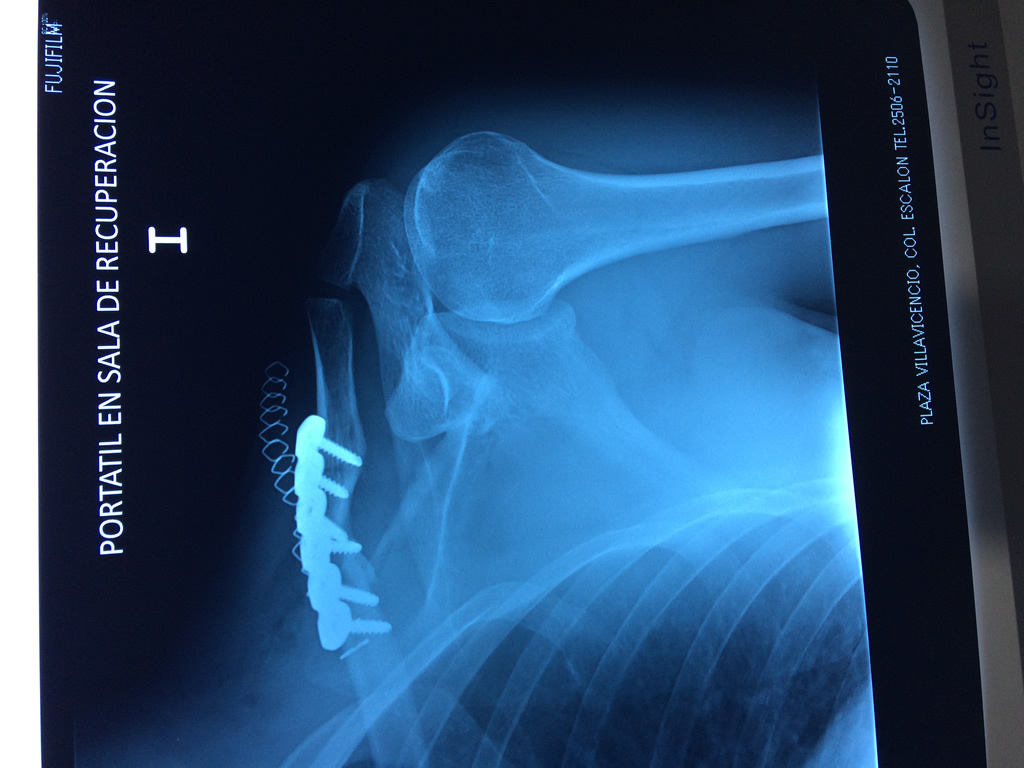

Calcaneo - Clavícula

La clavícula es un hueso largo, con forma de "S" itálica, situado en la parte anterosuperior del tórax. Junto con la escápula forman la cintura escapular. Se puede palpar por toda su longitud y se extiende del esternón al acromion de la escápula, siguiendo una dirección oblicua lateral y posterior.